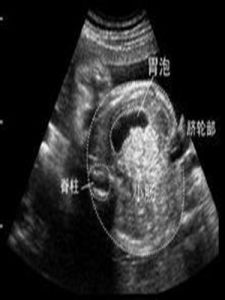

胎兒胃泡稍大一般見於 兩種情況:

1、胎兒先天性幽門肥厚,這種情況多伴有胃腔增大,胃內容物增多表現,並且胃泡增大是逐漸增大。

2、是一過性增大,也稱暫時性胃泡增大,是胃內容物暫時儲留,並分解產生過多氣體造成,僅一次檢查,還不能確定是那一種情況引起,建議你一周后複查一下。從測量數據看胎兒發育情況屬正常。現在懷孕37周,臍帶繞頸是常見現象,一般不會有問題,胎兒在腹內是不斷轉動的,到臨產時,一般會自己轉回來,但也不能麻痹,應勤複查,自己平常多注意胎動,有條件可勤聽胎心,發現異常情況,及時到醫院檢查。